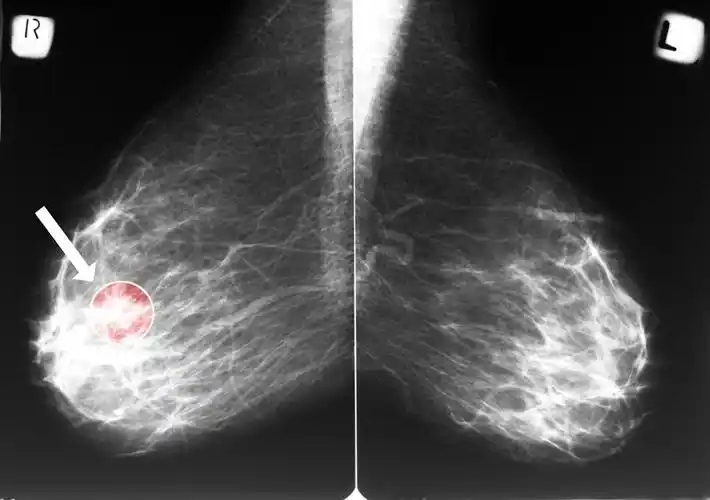

如何揪出乳腺结节?